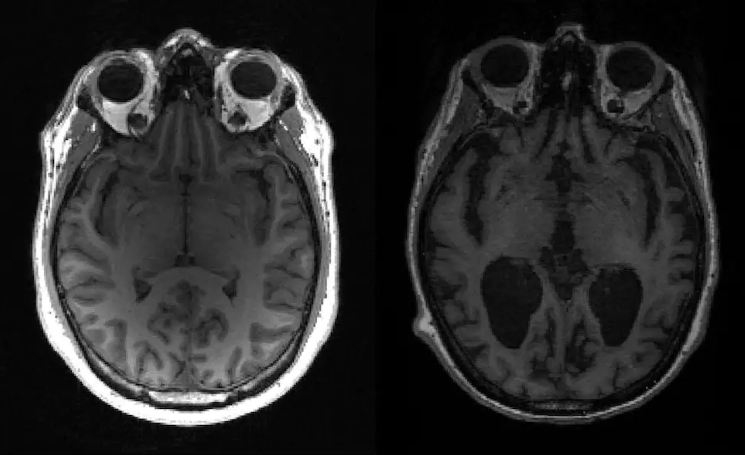

For a long time, MRI brain scans have been a key tool in diagnosing and understanding Alzheimer's disease. At the same time, we've also seen artificial intelligence (AI), particularly deep learning models, making a difference in various areas of medicine, including helping us answer many questions about the brain [5]. In our recently published work in Communications Medicine, we put forward an approach that harnesses AI and structural MRI brain scans to spot patterns of brain shrinkage that look like Alzheimer’s disease, but crucially in healthy individuals. This identifies a high-risk group that are likely to go on to Alzheimer's disease — exactly the group for recruitment to prevention studies and disease-modifying treatment trials.

Our AI-based analysis found people in the UK Biobank group who showed neuroimaging patterns similar to Alzheimer's, even though they didn't have a diagnosis or any reported symptoms of dementia. These people had an Alzheimer's-like pattern of brain shrinkage, indicating a high risk of developing the disease later on.